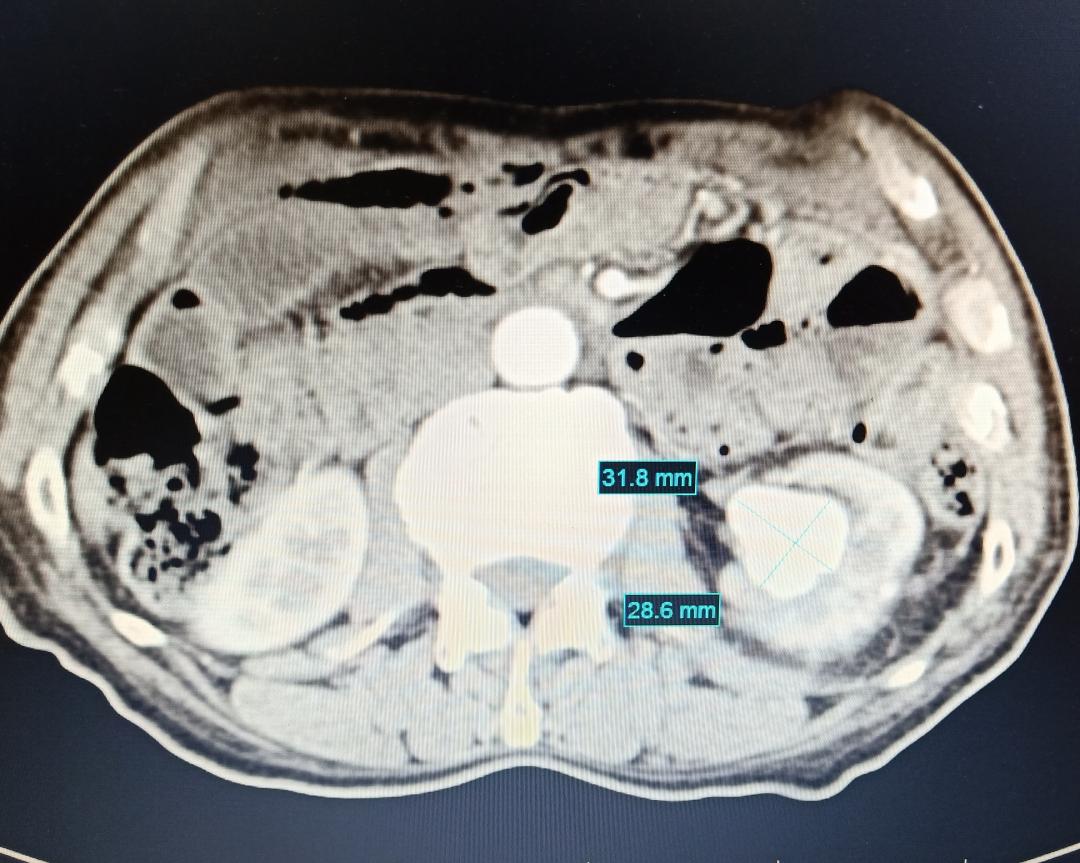

王先生检查时发现肾脏动脉瘤,肾动脉扩张到3厘米多,随时有破裂大出血风险!他辗转找到门头沟区医院肿瘤与介入科主任陈力强,决定接受肾动脉瘤栓塞术。

介入手术在局部麻醉下进行,腹股沟插管后动脉造影:肾动脉末梢瘤样扩张。